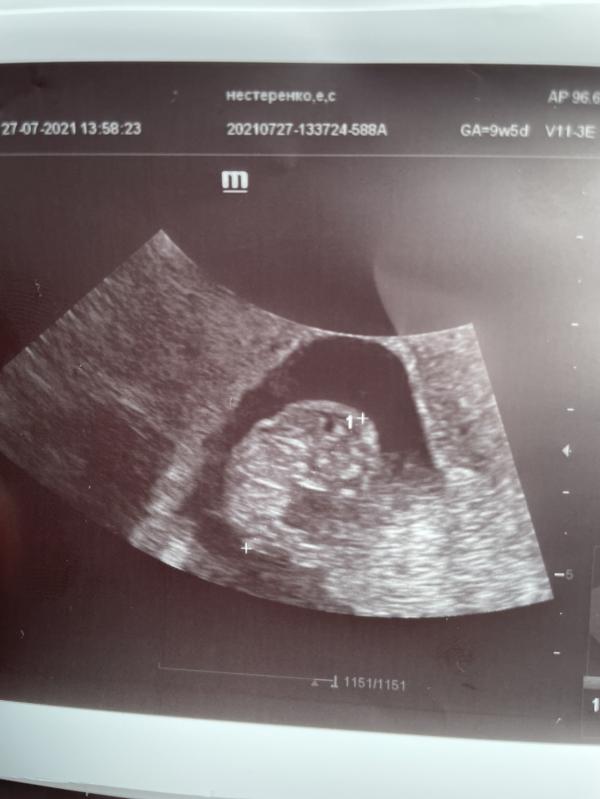

Опять закровила с утра, съездила на узи. Малыш растет, 2,2 см уже ❤️ гематома тоже растет 😾 13 мл крови 😾 возобновлять транексам, сказала долго еще кровить будет. Отстаем на 6 дней, но так и было все прошлые узи. Так что срок не 9,5 а 8,6 нед фактически. Половой и физический покой, естественно, ходить можно, но поднимать ничего нельзя. Буду ждать теперь скрининг